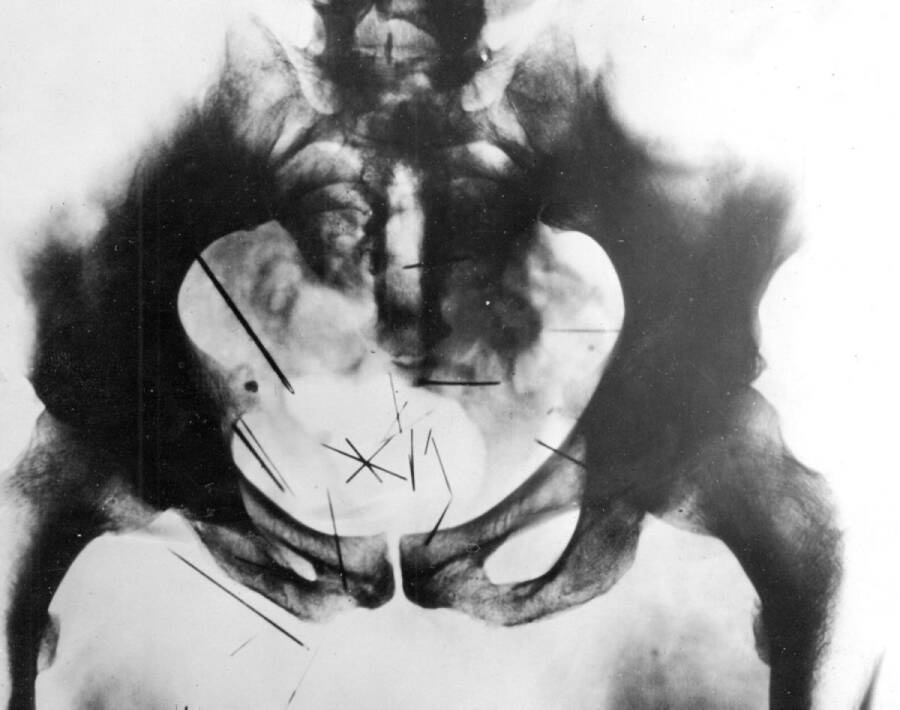

Две години по-късно Албърт започнал нездравословна връзка с по-голямо момче, което го научило да консумира човешки изпражнения. Той също така развил обсесия към сексуалното членовредителство, като редовно набучвал игли в слабините и корема си и се бичувал с гребло с пирони. По-късна рентгенова снимка на таза му разкрила, че в плътта му имало 29 игли.

Рентгенова снимка на таза на Фиш с 29 игли, забодени в него